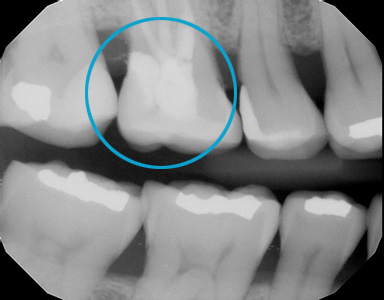

Biomimetic Dentistry :

Restore your tooth back to its original form with a tooth-like material.

Amalgam Replacement

Replaces bad amalgam fillings with a tooth-like material. Restores the tooth to its original look. No red gum and trapping of food particles anymore. It provides a better appearance and better function.

Amalgam replacement with Cerec Onlay.

Creates long-lasting teeth by preserving more teeth structure in a biomimetic way!